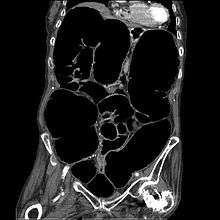

Ogilvie syndrome is the acute dilation of the colon in the absence of any mechanical obstruction in severely ill patients.[1]

Colonic pseudo-obstruction is characterized by massive dilatation of the cecum (diameter > 10 cm) and right colon on abdominal X-ray.[2][3] It is a type of megacolon, sometimes referred to as "acute megacolon," to distinguish it from toxic megacolon.